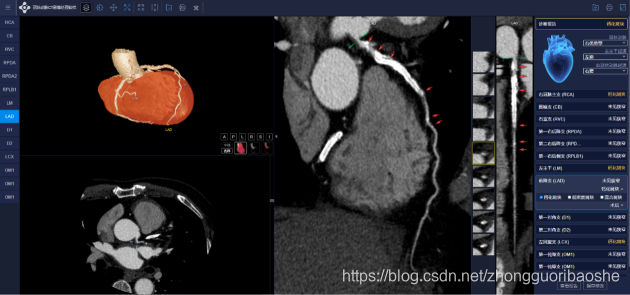

医生仅需一次点击即可进入AI界面,多模态图像及分析界面将同时显示,客户端界面右侧提供了极为丰富的冠脉诊断提示,涵盖了对目前临床常见解剖变异及狭窄斑块等病变的全面分析,并可一键式生成冠脉CTA结构化报告以及钙化积分报告,给到医生专业、规范、快捷的医学信息化服务。

冠脉CTA智能分析系统产品界面